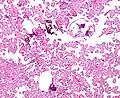

Micrograph of a choroid plexus papilloma. H&E stain. Micrograph of a choroid plexus papilloma. H&E stain.

The tumor is neuroectodermal in origin and similar in structure to a normal choroid plexus. They may be created by epithelial cells of the choroid plexus.